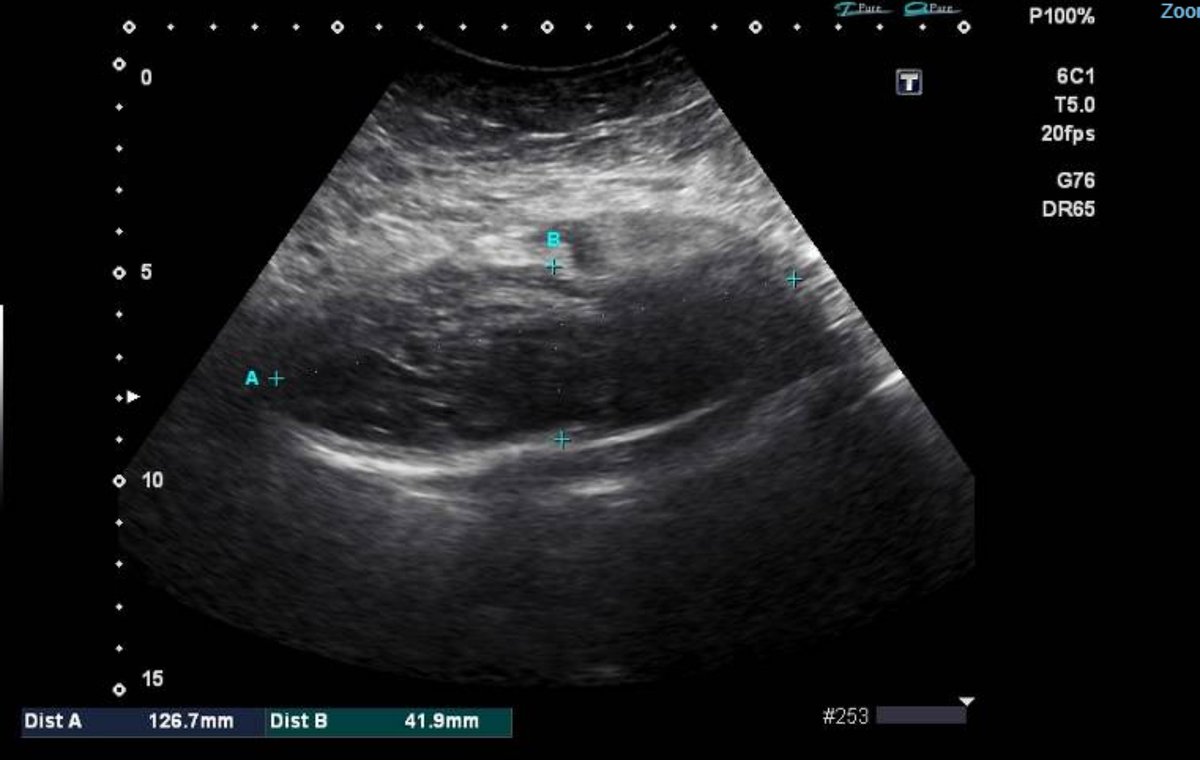

muscular hematoma An 84-year-old with morbid obesity, type 2 resp failure, admitted with acute dropping of hemoglobin to 6 gm and right abdominal pain. POCUS showed right abd muscular huge hematoma

CT abd confirmed an intramuscular and intraperitoneal hematoma. Most probably related to dual antiplatelet and cough